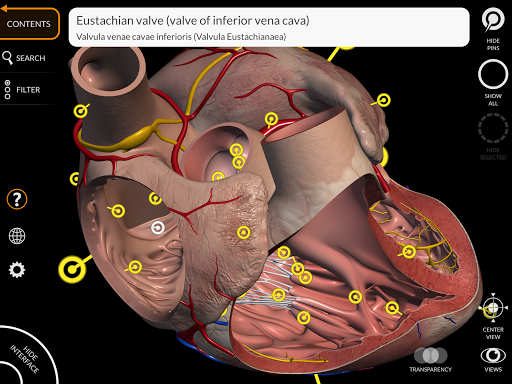

"Anatomía - Atlas 3D" permite estudiar la anatomía humana de forma fácil e interactiva.

A través de una interfaz sencilla e intuitiva es posible observar cada estructura anatómica desde cualquier ángulo.

Los modelos anatómicos 3D son especialmente detallados y con texturas de hasta una resolución de 4k.

La subdivisión por regiones y las vistas predefinidas facilitan la observación y el estudio de partes individuales o grupos de sistemas y las relaciones entre los diferentes órganos.

MODELOS ANATÓMICOS 3D

• Sistema cardiovascular • Sistema

nervioso • Sistema respiratorio • Sistema digestivo • Sistema urogenital (masculino y femenino) • Sistema endocrino • Sistema linfático • Sistema ocular y auditivo CARACTERÍSTICAS • Interfaz sencilla e intuitiva • Rotar y hacer zoom en cada modelo en el espacio 3D • Opción para ocultar o aislar uno o varios modelos seleccionados • Filtro para ocultar o mostrar cada sistema • Función de búsqueda para encontrar fácilmente cada parte anatómica • Función de marcador para guardar vistas personalizadas • Rotación inteligente que mueve el centro de rotación automáticamente • Función de transparencia • Visualización de músculos a través de niveles de capas desde las superficiales hasta las más profundas • Al seleccionar un modelo o un pin, aparece el término anatómico relacionado • Descripción de los músculos: origen, inserción, inervación y acción • Mostrar/ocultar interfaz de usuario (muy útil con pantallas pequeñas) MULTILINGÜE • Los términos anatómicos y la interfaz de usuario están disponibles en 11 idiomas: latín, inglés, francés, alemán, italiano, portugués, turco, ruso, español, Chino, japonés y coreano • Los términos anatómicos se pueden mostrar en dos idiomas simultáneamente REQUISITOS DEL SISTEMA • Android 8.0 o posterior, dispositivos con al menos 3 GB de RAM Reversi